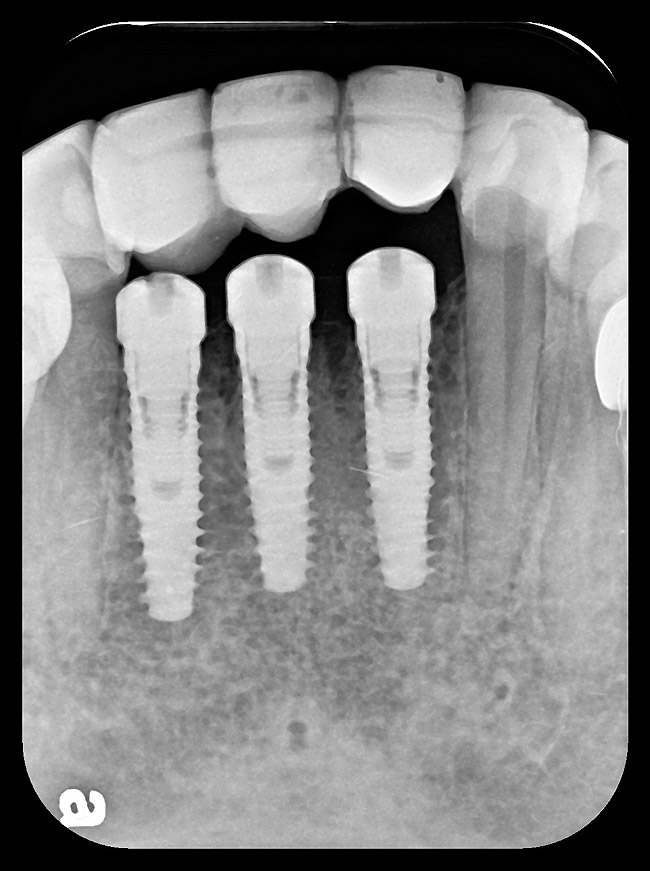

Figure 9: Implants supporting zirconia abutments and crowns, site Nos. 24 through 26—periapical view.

Figure 9

Six months later, the periodontist prepared osteotomies and placed three 3.25-mm x 13-mm implants using a vacuum-formed surgical guide fabricated by the restorative dentist (using a cast of the provisional bridge as a guide, as described by Block et al16); healing abutments were placed simultaneously. A post-implant radiograph confirmed good implant alignment with the pontics of the provisional from teeth Nos. 22 through 28 (Figure 6).

After the zirconia abutments were torqued to 20 Ncm, cotton and composite were used to cover the screw access openings. Figure 7 and Figure 8 show the finished feldspathic porcelain crowns on implants in sites Nos. 24 through 26, and on teeth Nos. 22, 23, 27, and 28; all crowns were cemented with dual-cure resin cement. Good remodeling of gingival architecture is also apparent in Figure 7. As predicted, the free gingival margin (FGM) on No. 23 is approximately 2 mm coronal to those of the adjacent implant crowns on Nos. 24 through 26 (Figure 7); as per the patient’s initial statement, this discrepancy was not an esthetic concern to her. Figure 9 shows the final post-restoration periapical view.